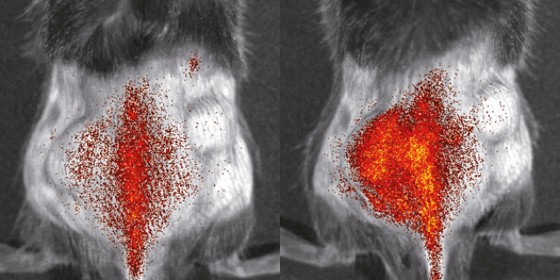

Verteilung von Immunzellen im Körper einer Maus, aufgenommen mit der optischen Bildgebung<address>© S. Gran & L. Honold et al./Theranostics 2018(8)</address>

Bereits seit Jahren arbeiten die WWU-Forscher an Techniken, mit denen sie Dynamiken und Wechselwirkungen von Immunzellen in lebenden Organismen bestmöglich sichtbar machen können. Hierzu nutzen sie und ihre internationalen Kollegen unter anderem die Positronen-Emissions-Tomographie und die optische Bildgebung. Ein großes Ziel des jetzt anlaufenden Projekts ist es, geeignete Methoden zu entwickeln, mit denen Immunzellen vor, während und nach einer Immunbehandlung beobachtet werden können. Dabei sehen sich die Forscher die Vorgänge zunächst in tierischen Krankheitsmodellen an – mit dem Ziel, die Ergebnisse und Methoden zeitnah auf Patienten zu übertragen und letztendlich Immuntherapien bei Krankheiten wie Krebs oder Entzündungen „bildgesteuert“ zu verbessern.